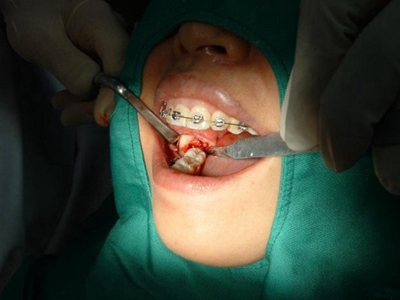

智齿冠周炎牙龈高度肿胀图

患有智齿冠周炎的智齿旁边牙龈发生高度肿胀,明显隆起于周围黏膜,触之质地柔软,并有明显触痛。建议患者积极控制炎症,并及时拔除智齿。